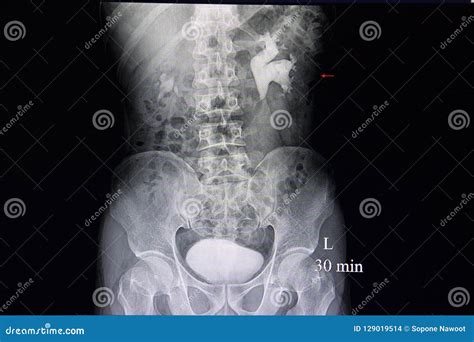

Diagnosing hydronephrosis involves a combination of medical history, physical examination, and diagnostic tests. The goal is to identify the underlying cause of the obstruction and determine the best course of treatment. Common diagnostic tests include:

• Intravenous Pyelogram (IVP): A test that involves injecting a contrast dye into the bloodstream to visualize the urinary tract.